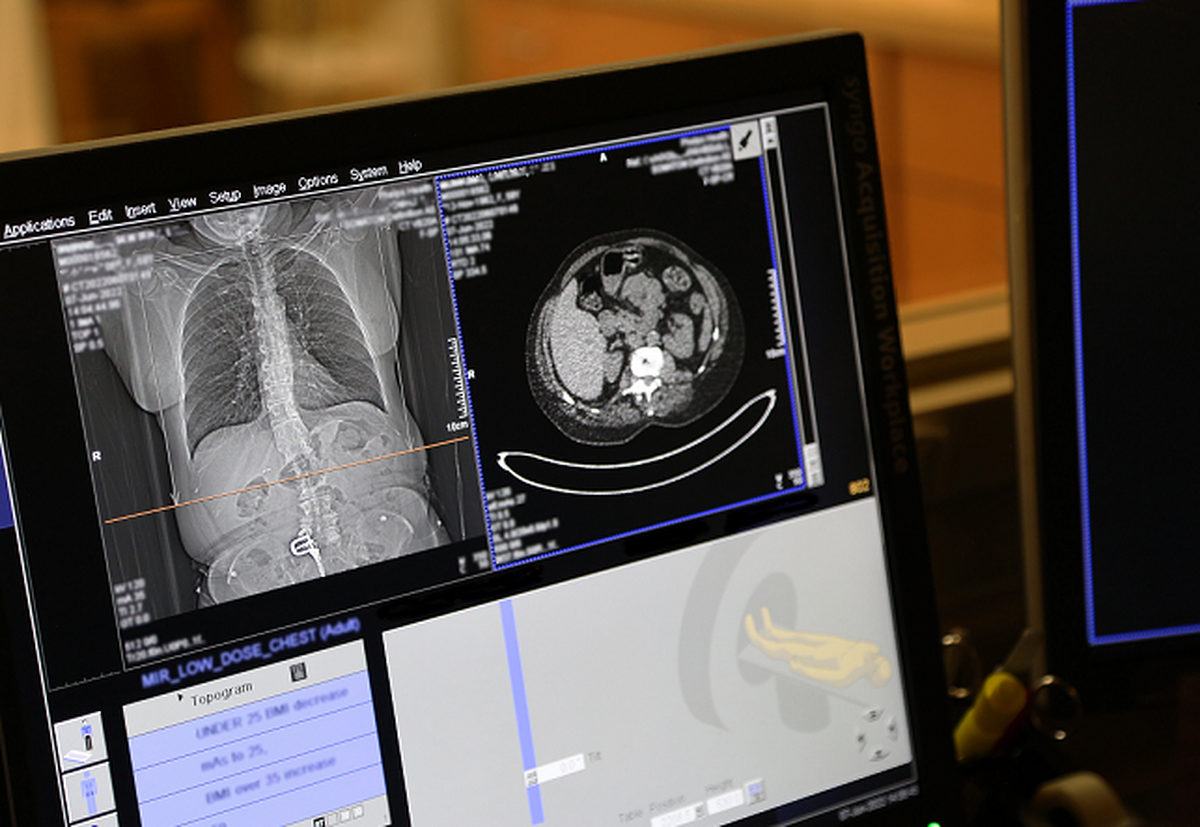

کاظمی زاده: درمان سرطان ریه بستگی به مرحله‌ی تشخیص بیماری دارد و پزشکان برای تعیین میزان پیشرفت آن از روش‌های تصویربرداری پیشرفته استفاده می‌کنند.

کاظمی زاده: یکی از اقدامات مهم برای تشخیص زودهنگام سرطان ریه، غربالگری منظم در افراد پرخطر است. افرادی که بیش از ۲۰ پاکت سیگار در سال مصرف کرده‌اند (در طول عمر خود)، و بیش از ۵۵ سال سن دارند، حتماً تحت نظر پزشک و با استفاده از روش‌های تصویربرداری مانند سی‌تی‌اسکن کم‌دوز (Low-dose CT scan) غربالگری شوند.